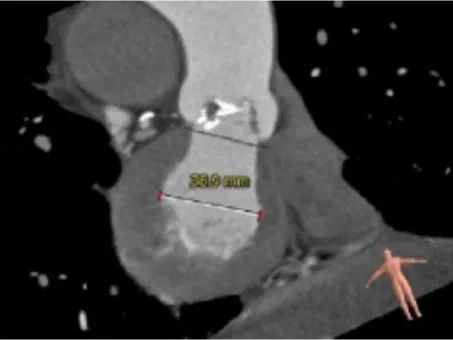

主动脉根部测量:

ANNULUS

SOV DIAMETER

LVOT

STJ

ASCENDING AORTA

LEFT VENTRICLE